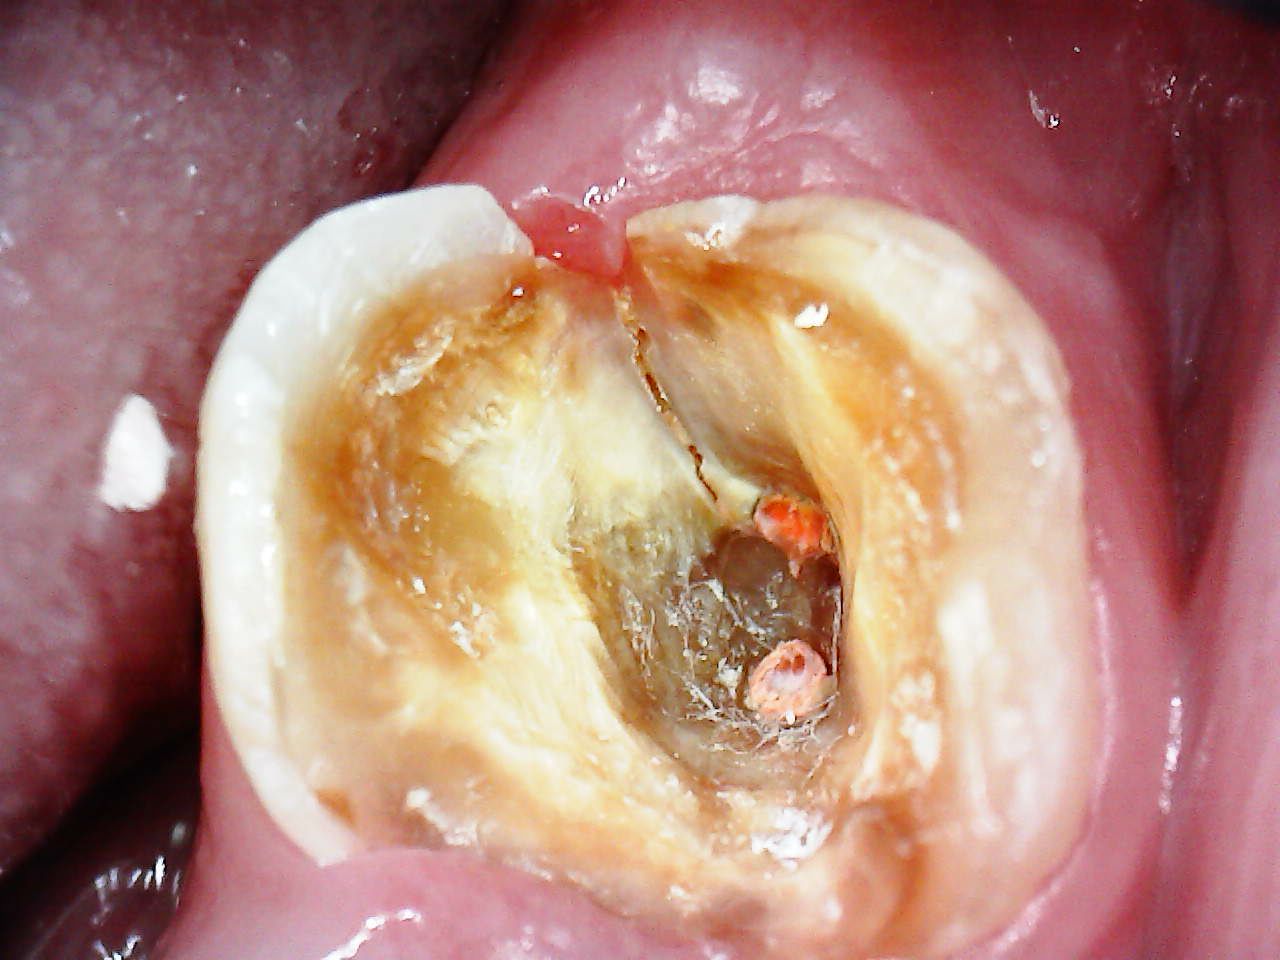

Perfurações, desgaste e anatomia interna visível na abertura do dente

Trincas, fraturas e infiltrações ficam extremamente evidentes com a ampliação da SkyCam.

Exemplos reais de uso da SkyCam na Endodontia